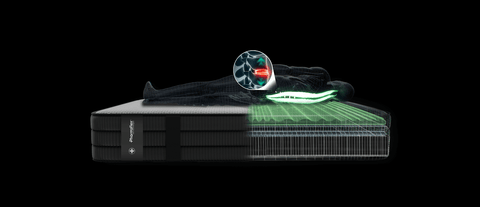

Questa procedura misura come il peso del corpo viene distribuito sulla superficie di riposo. Durante l'analisi, un individuo si sdraia sul prodotto, e con l'ausilio di tecnologie avanzate si rilevano le zone dove il corpo esercita maggior pressione. Questo permette di identificare aree a rischio di stress o disagio, come le spalle, i fianchi o la zona lombare.

Attraverso strumenti all'avanguardia ci impegniamo a monitorare il corretto allineamento del rachide cervicale in ogni posizione di riposo. Lo scopo è di assicurarci che non si verifichino condizioni che possano portare ad uno scompenso muscolare o scheletrico.

Decompressione vertebrale

Questo test avanzato ad alta precisione ha lo scopo di monitorare la colonna vertebrale prima e dopo l'utilizzo dei nostri prodotti. Confrontando i risultati rispetto ad altri prodotti, i nostri ingegneri biomedici possono valutare con precisione quanto efficacemente l'azione dei dispositivi abbia alleviato la compressione sui dischi e le vertebre.